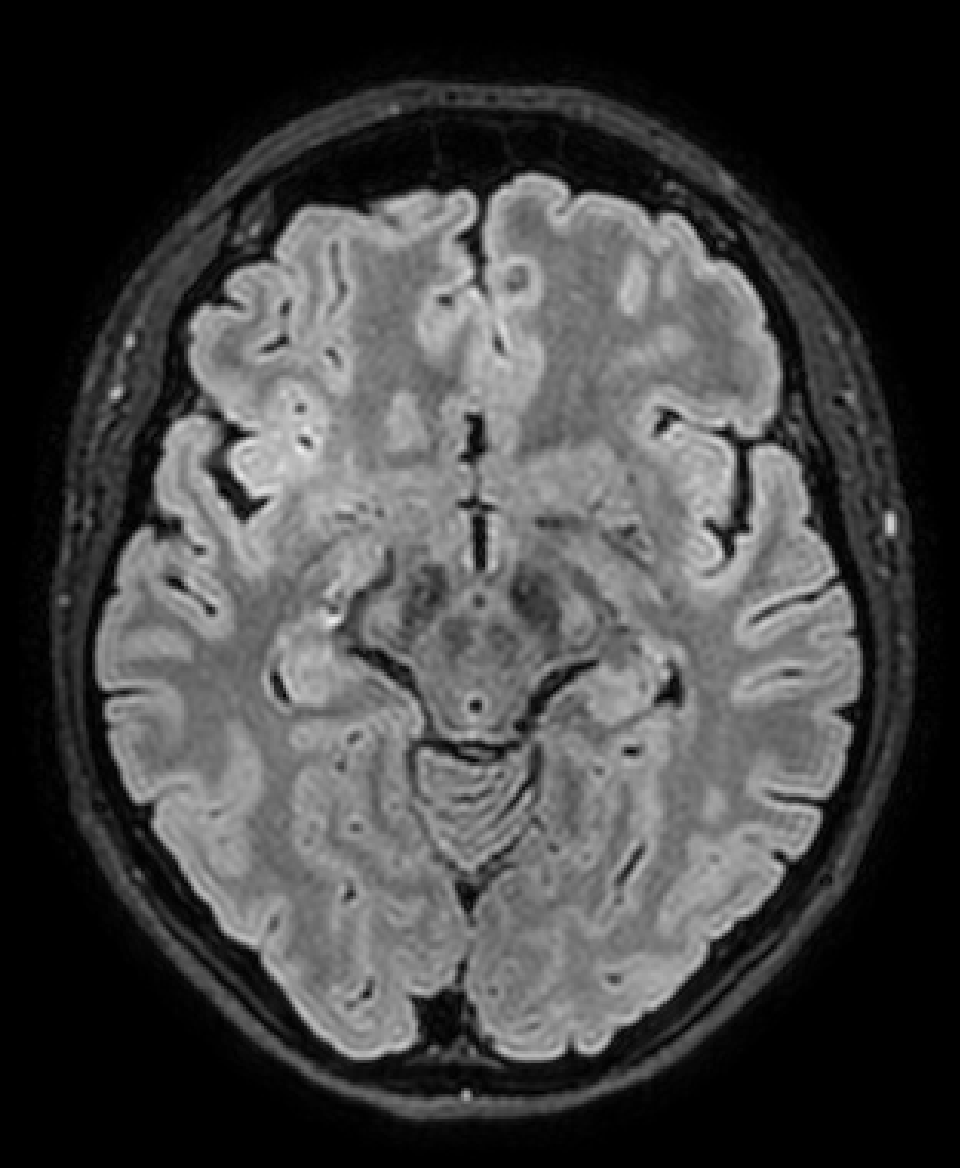

What do we see?

Some low signal on frontal lobe....

Some steps from visual to numerical assessment:

1. Mean per VOI

| VOI | Mean value |

|---|---|

| Frontal L | 121.3 |

| Frontal R | 149.1 |

| Occipital L | 297.1 |

| Occipital R | 279.7 |

| WM | 98.1 |

| Cerebellum GM | 137.3 |